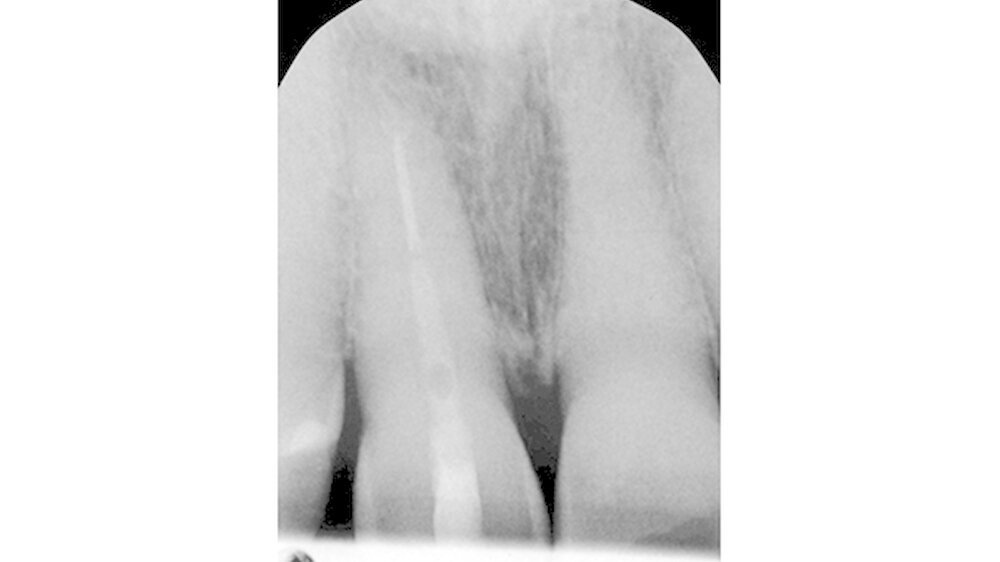

Während die palatinale Fläche unbeschädigt war, zeigte die bukkale Fläche eine vertikale Frakturlinie (Abbildung 3), die mit einem feinen diamantierten Schleifkörper erweitert wurde (Abbildung 4). Zusätzlich erfolgte die Entfernung des retrograden Wurzelkanalfüllmaterials. Beide Defekte wurden mit Biodentine (Septodont, Niederkassel) aufgefüllt (Abbildung 5).